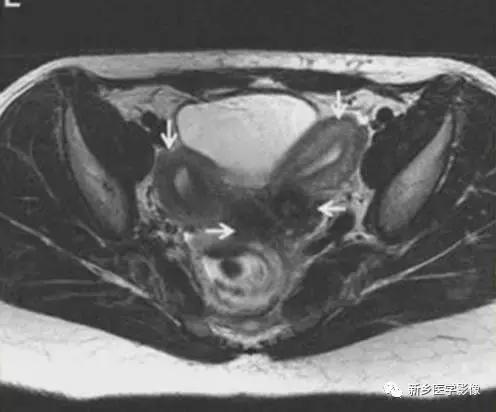

上图:单角子宫(II-B残角,有内膜腔,不相通):右侧残角宫腔内积血,为短T1长T2异常信号。左侧单角子宫,见带状结构,呈香蕉样。

上图:II-D无残角:右侧单角子宫,左侧无残角